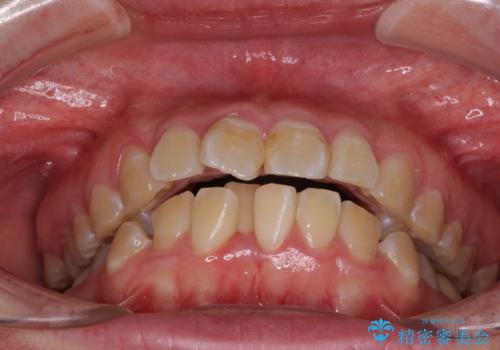

- 口元の閉じにくさと、前歯のでこぼこの歯並びを気にして来院された患者様です。

口元を積極的に引っ込めるために、上下左右の小臼歯計4本を抜歯することとしました。

4本の歯を抜歯したことで、飛び出していた口元が引っ込み、横顔が大きく改善されました。